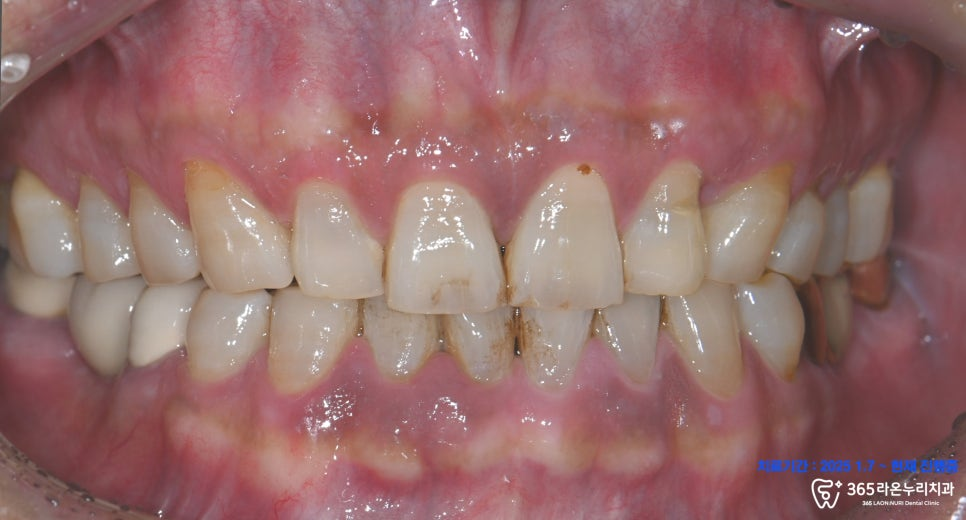

치근단 사진과 엑스레이 사진에서 확연하게

원심 치근의 골소실이 관찰되어,

정밀 진단을 위한 CT 촬영을

진행했습니다.

그러자 CT 사진에서 골소실

부위가 명확하게 나타나고 있었는데요.

이렇게 염증으로

골이 소실되는 현상을

치주염이라 합니다.